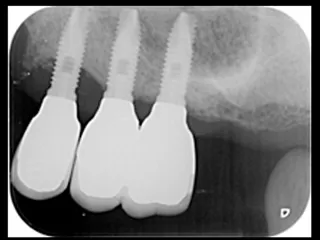

CASE No.1 奈良 嘉峰 先生(神奈川県茅ヶ崎市開業)

施 術 前 (レントゲン写真)

施 術 後 (レントゲン写真)